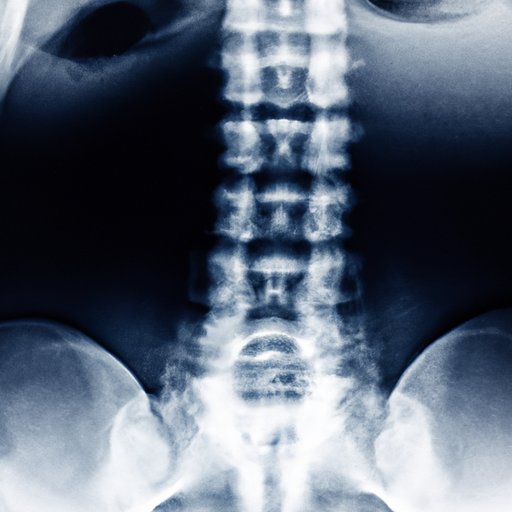

X-rays have a broad range of practical applications, with their use in medical imaging being one of the most prevalent. They allow doctors and medical professionals to view internal bodily structures and diagnose medical conditions. Other applications of x-rays include materials testing, airport security checks, and industrial inspection. The ability of x-rays to travel in straight lines is essential for their use in medical procedures, as it allows for accurate imaging and diagnosis.

The concept of x-ray absorption is used in medical imaging to produce high-contrast images of bodily structures. X-rays interact with matter, causing a reduction in their energy and ultimately being absorbed. The amount of absorption can vary among different types of tissues, resulting in differences in contrast when imaged. This allows for the creation of detailed images of specific structures within the body, such as the bones or vital organs.